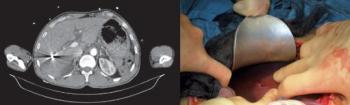

16.4. ábra. Mellkascsövezés és pericardium-punctio robbanásos sérültön

(a szerző felvétele)